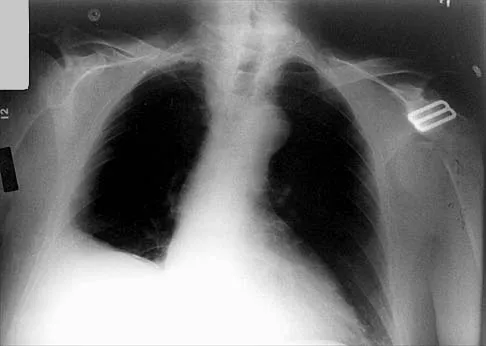

Question 64

Which of the following findings is seen in the chest radiograph shown in Figure 13?

Explanation